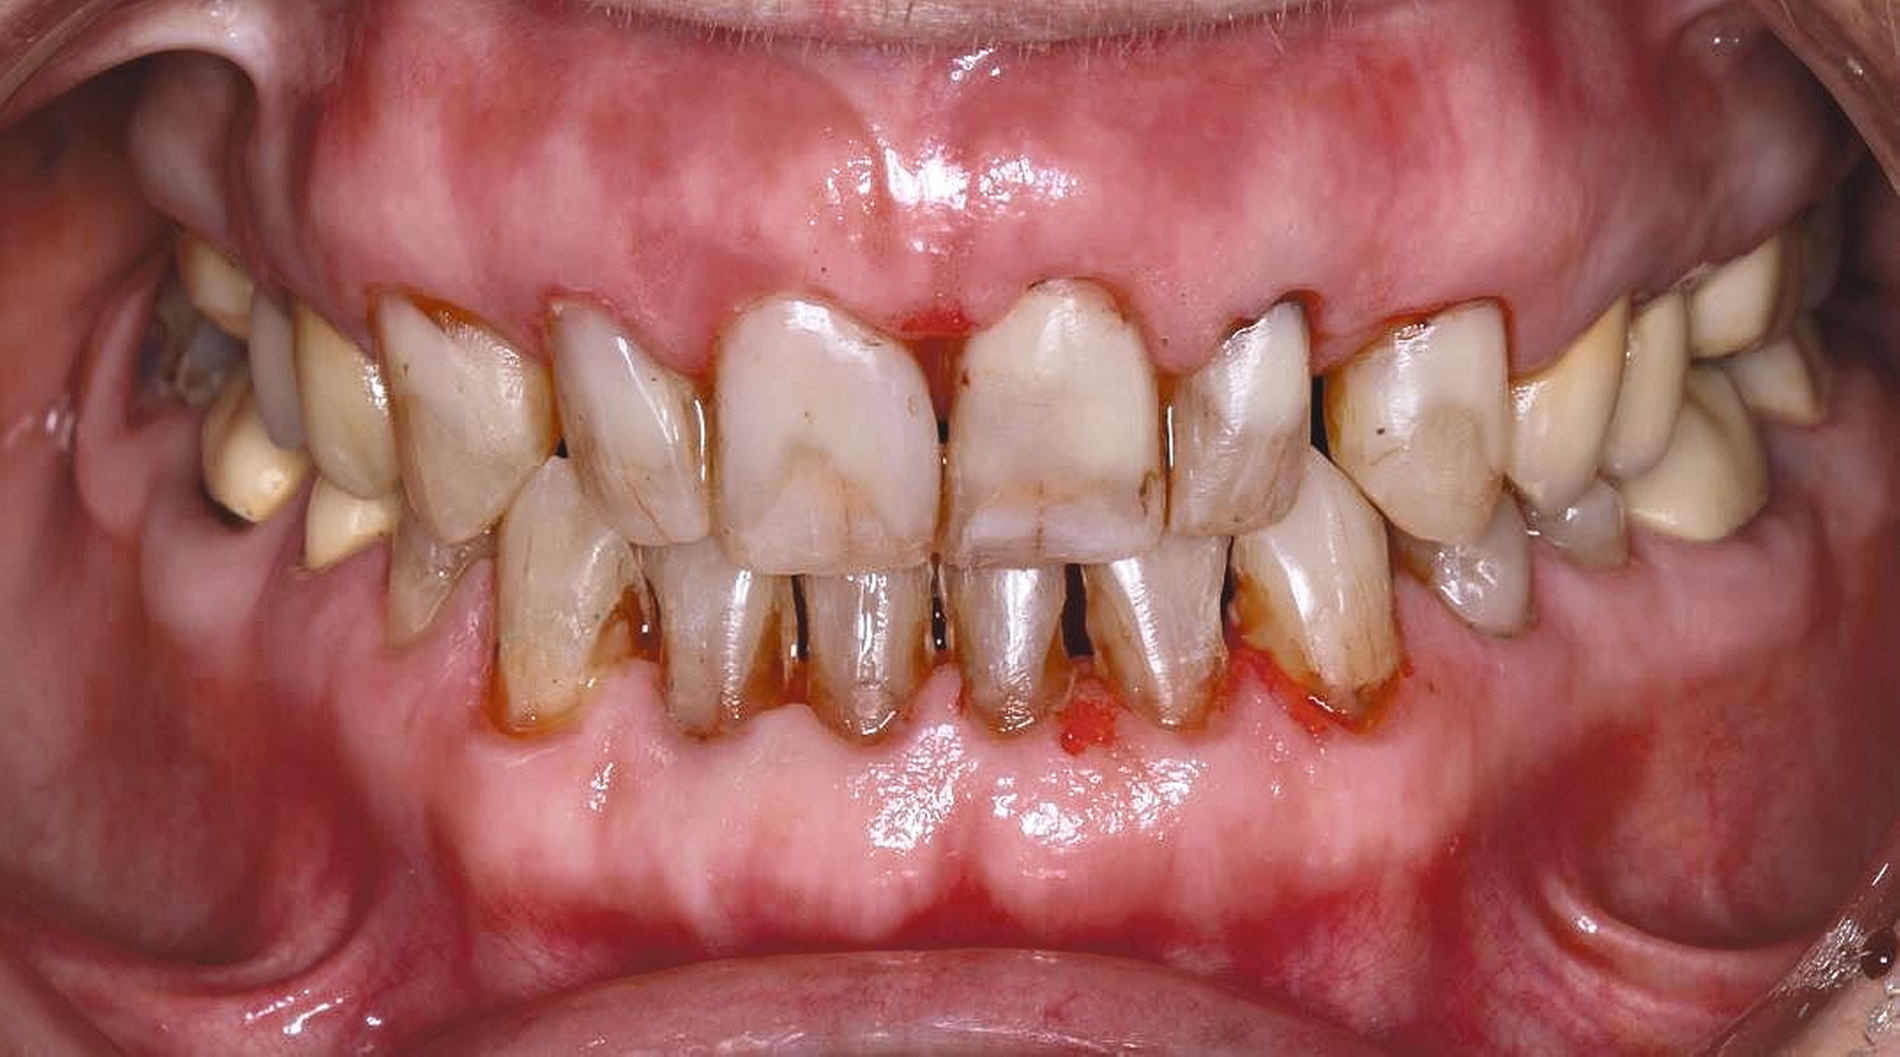

Auch aufseiten der Pflege wurden durch die Einführung des DNQP-Expertenstandards Rahmenbedingungen zur Verbesserung der Mundgesundheit bei Personen mit Pflegebedarf geschaffen. Der Expertenstandard definiert unter anderem das Aufgabenspektrum, den Verantwortungsbereich und das nötige Kompetenzprofil von Pflegefachpersonen in Bezug auf die Mundgesundheit bei Personen mit Pflegebedarf. Als zentrale Anforderung an Pflegefachpersonen formuliert der Expertenstandard zudem die Kompetenz, einschätzen zu können, wann weitere zahnmedizinische Expertise hinzuzuziehen ist [Sirsch et al., 2022]. Um die Maßnahmen zur Förderung der Mundgesundheit nachhaltig zu implementieren, ist ein dauerhafter Austausch zwischen Zahnmedizinern und Pflegeverantwortlichen, unter regelmäßiger Einbeziehung geriatrisch-hausärztlicher Expertise notwendig. Die Telemedizin verspricht in Bezug auf die Verbesserung des Zugangs zu zahnmedizinischen Leistungen für Personen in Pflegeeinrichtungen Zukunftspotenzial [Aquilanti et al., 2020]. Nicht in allen Fällen sind Defizite der Mundhygienefähigkeit absehbar. Nach Unfällen oder Schlaganfällen sind Patientinnen und Patienten eventuell von einem auf den anderen Tag nicht mehr in der Lage, ihre Mundhygiene selbstständig adäquat durchzuführen (Abbildung 4).

Patientinnen und Patienten mit stark reduzierter Therapiefähigkeit profitieren in besonderem Maß von zeiteffektiven Methoden und Materialien, zum Beispiel Bulk-fill-Kompositen, Reparaturfüllungen, Glasionomerzementen oder Intraoralscans. Die Therapiefähigkeit kann – ähnlich wie in der Kinderzahnmedizin – durch ein vertrauensvolles Verhältnis optimiert werden. Anders als in der Kinderzahnmedizin gibt es in der Alterszahnmedizin aber keine altersassoziierten Kontraindikationen für zahnmedizinische Interventionen. Voraussagbare Therapieergebnisse sind von besonderer Bedeutung, um erneute Behandlungen zu vermeiden. Das gesamte Spektrum zahnmedizinischer Interventionen kann bei der Behandlung von Personen mit Pflegebedarf sinnvoll sein. Die Abbildungen 6 bis 9 zeigen zahnmedizinische Interventionen bei Personen mit ausgeprägter Frailty (Stufe 7 der klinischen Frailty-Skala).